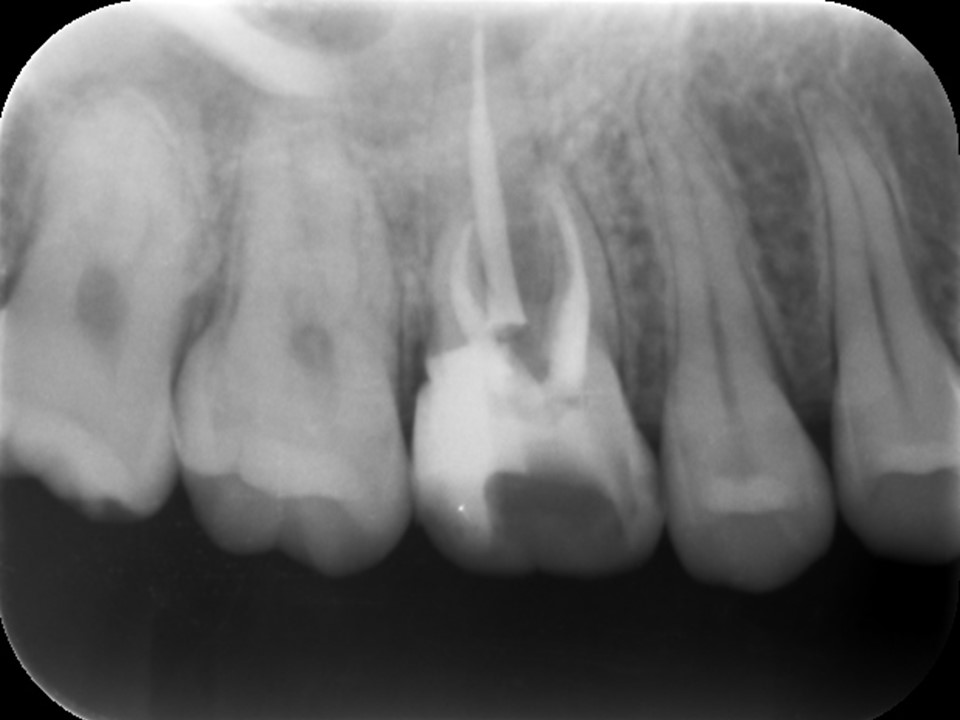

右上の6番の大臼歯に、大きなコンポジットレジン充填がしてありました。レントゲンおよびCT診査を行ったところ、歯髄に達する大きな充填の跡が見られ、根尖部の骨はすでに大きく溶けて吸収しており、炎症は副鼻腔に達していました(下写真)。レントゲンおよびCT画像から、虫歯治療後の歯髄壊死・壊疽から生じた慢性化膿性根尖性歯周炎と診断しました。また、根尖病変に起因する歯性上顎洞を併発していると診断しました。

治療前のレントゲンおよびCT画像です。右上6番には歯髄に達する大きなコンポジットレジン充填がされています。

根尖部の骨は黒く大きく溶け(赤矢印)、ほぼ上顎洞と交通しています。

上顎洞内部は上方までX線不透過性が亢進し(白くなっています)、典型的な上顎洞炎の像を呈しています(黄矢印)。